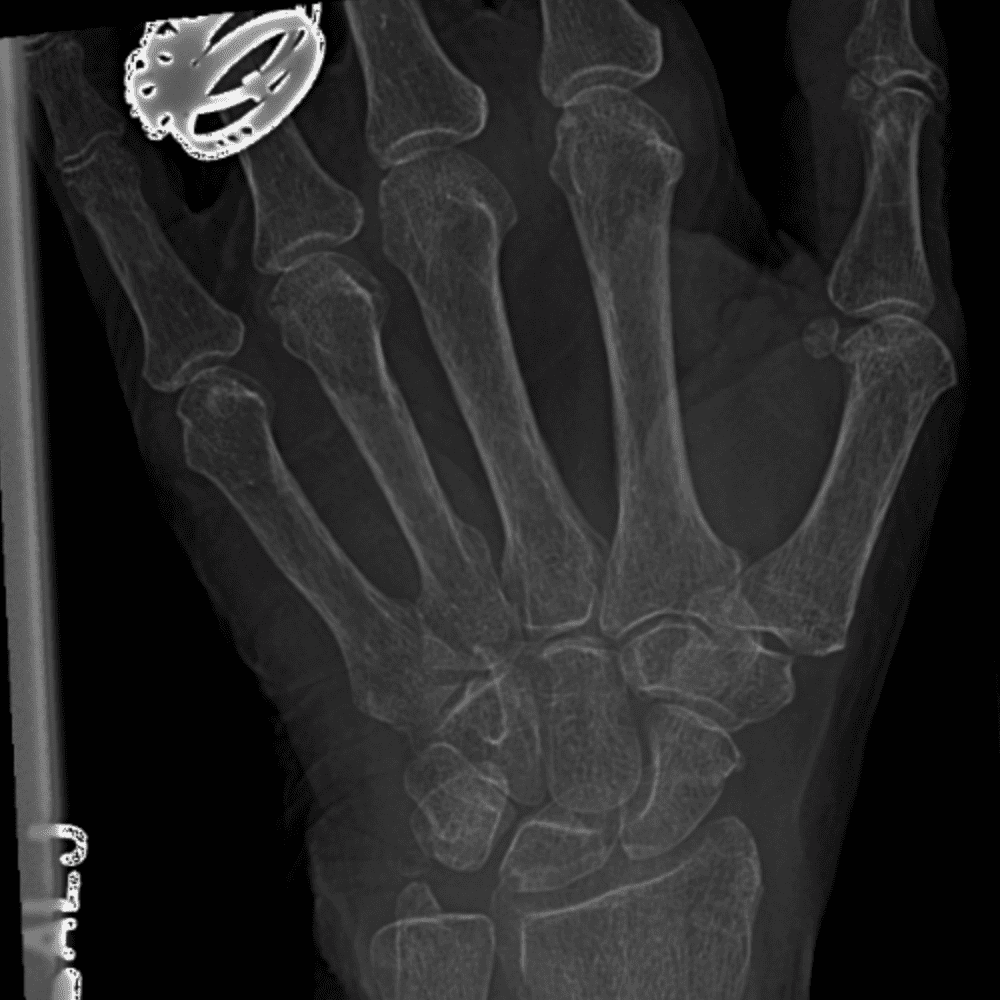

Simuliert den Dienst durch subtile oder schwierige Fälle und einige Normalbefunde.

30 Fälle